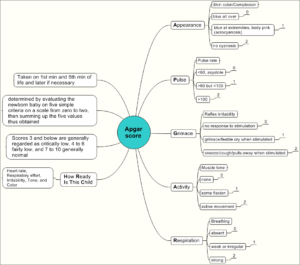

Maternal-Newborn Nursing

Cheatsheets

71

Mnemonics

24

Images

86

Picmonic

0